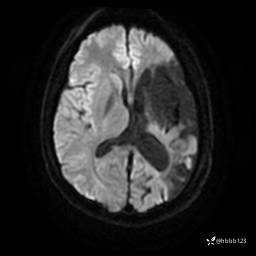

患者男,43岁。

简要病史:癫痫患者复诊,昨日发作5-6次,建议住院进一步治疗。

入院完善脑癫痫组合序列:

T2: